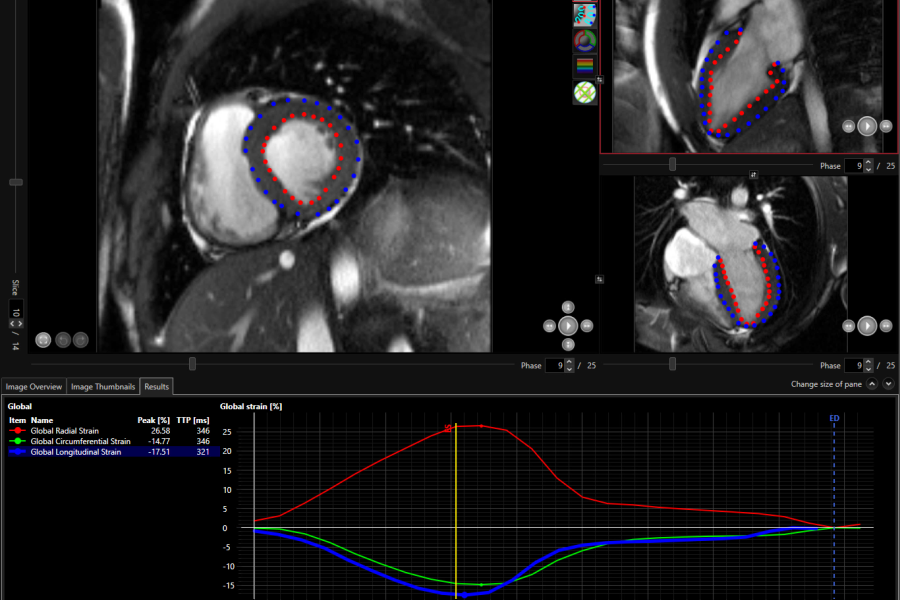

Caas MR Strain - part of Pie Medical Imaging’s CMR software platform - uses feature tracking to detect the ventricular deformation patterns and functional abnormalities of the heart wall. This can be analyzed before such abnormalities become obvious with conventional parameters. Caas MR Strain includes Global Longitudinal Strain (GLS) analysis, which has been proven to be more sensitive for systolic function assessment than Left Ventricular Ejection Fraction (LVEF).

• Three strain types are determined: longitudinal, circumferential, and radial;

• Global Longitudinal Strain including Peak Strain (%) and Time to Peak Strain (ms);